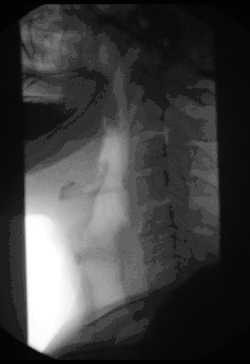

Fluoroscopy (/flʊəˈrɒskəpi/)[1], informally referred to as "fluoro", is an imaging technique that uses X-rays to obtain real-time moving images of the interior of an object. In its primary application of medical imaging, a fluoroscope (/ˈflʊərəˌskoʊp/)[2][3] allows a surgeon to see the internal structure and function of a patient, so that the pumping action of the heart or the motion of swallowing, for example, can be watched. This is useful for both diagnosis and therapy and occurs in general radiology, interventional radiology, and image-guided surgery.

Fluoroscopy has become an important tool in medical imaging to render moving pictures during a surgery or any other procedure.

Surgical fluoroscopy